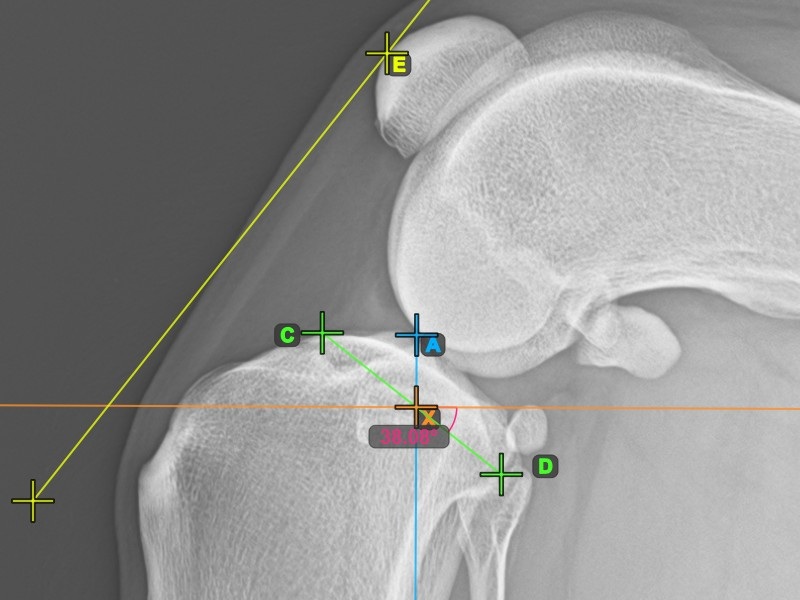

Vervollständigen Sie den TPA-Winkel, indem Sie den hintersten Punkt des Tibiakopfes (Tibiaplateau) markieren. Der TPA-Winkel wird automatisch als der Winkel zwischen der Linie, die die beiden Punkte am Tibiaplateau verbindet, und der senkrechten Linie zur Längsachse der Tibia berechnet.

Das Bild unten zeigt die übliche Platzierung des hintersten Punkts am Tibiaplateau und die automatisch berechnete TPA-Winkel-Messung.